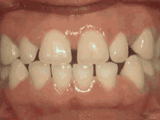

Phase I

Patient's parents were concerned about both aesthetics and the health of the erupting permanent teeth when they brought him to the orthodontist at age eight. The lower front teeth were crowded and they touched the palate, and the upper front teeth were extremely displaced from their normal positions. After twenty months of Phase I treatment with an expander and partial braces, patient's appearance and dental function was vastly improved.